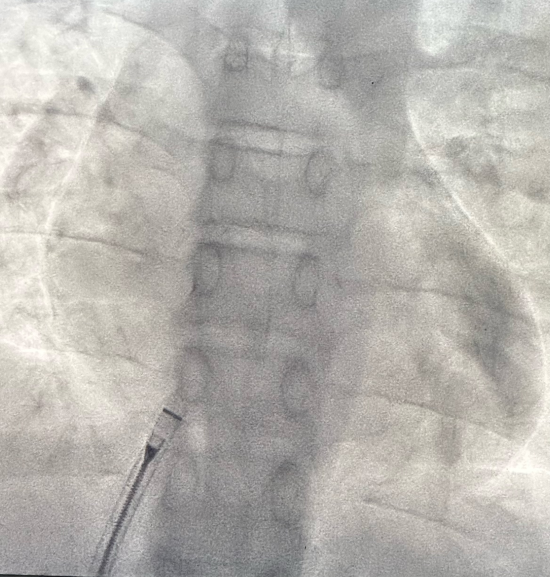

术后X线下无金属植入物

手术过程:精准微创,30分钟完成“补心”